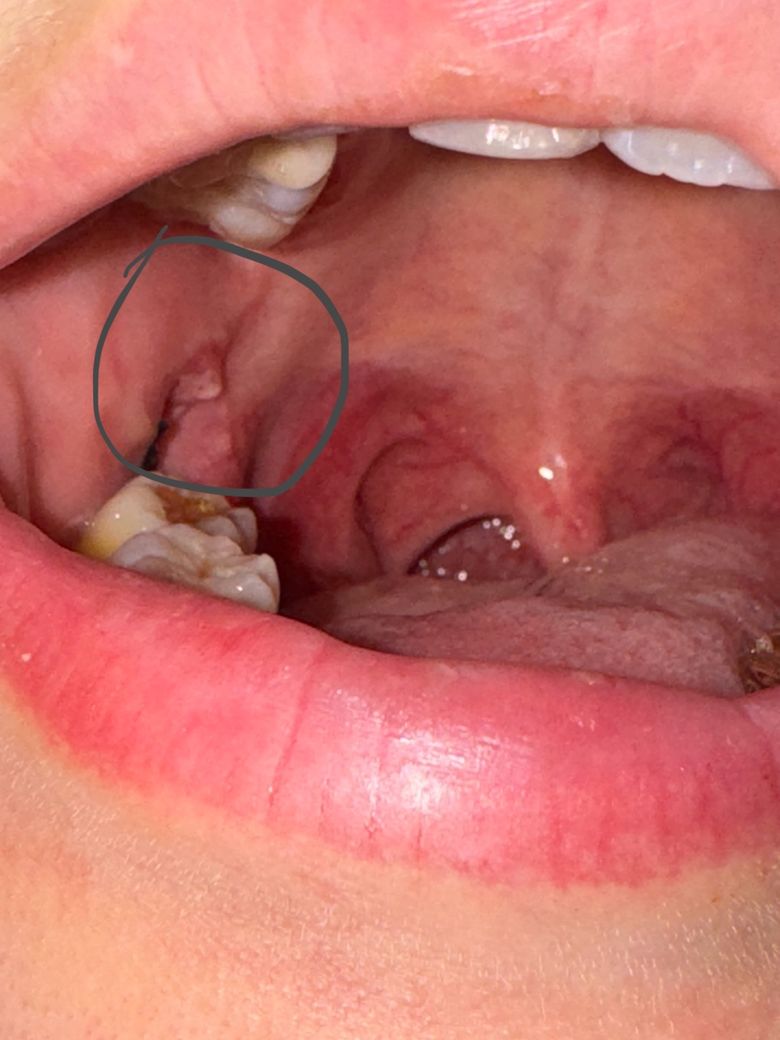

사랑니 자리 하얀 살이 올라와있는데 아픕니다

오른쪽 아래 매복 뽑았습니디

4일차인데 아파요ㅠㅠ

1번 사진이 둘쨋날이고

• 1번 째 사진